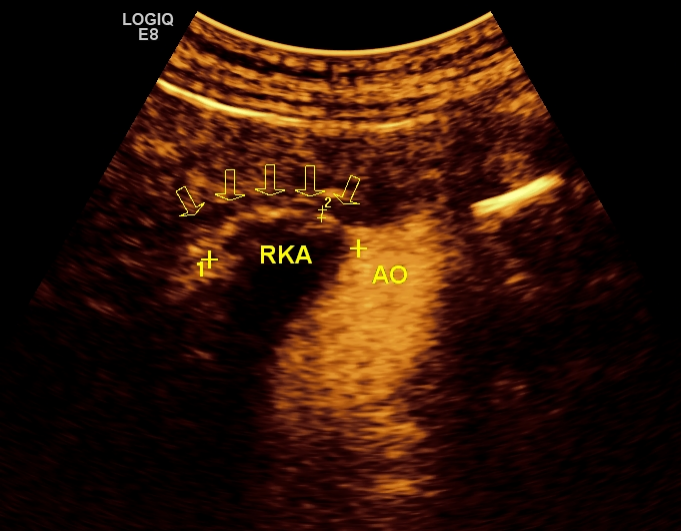

1    超声造影:显示正常右侧肾动脉全程